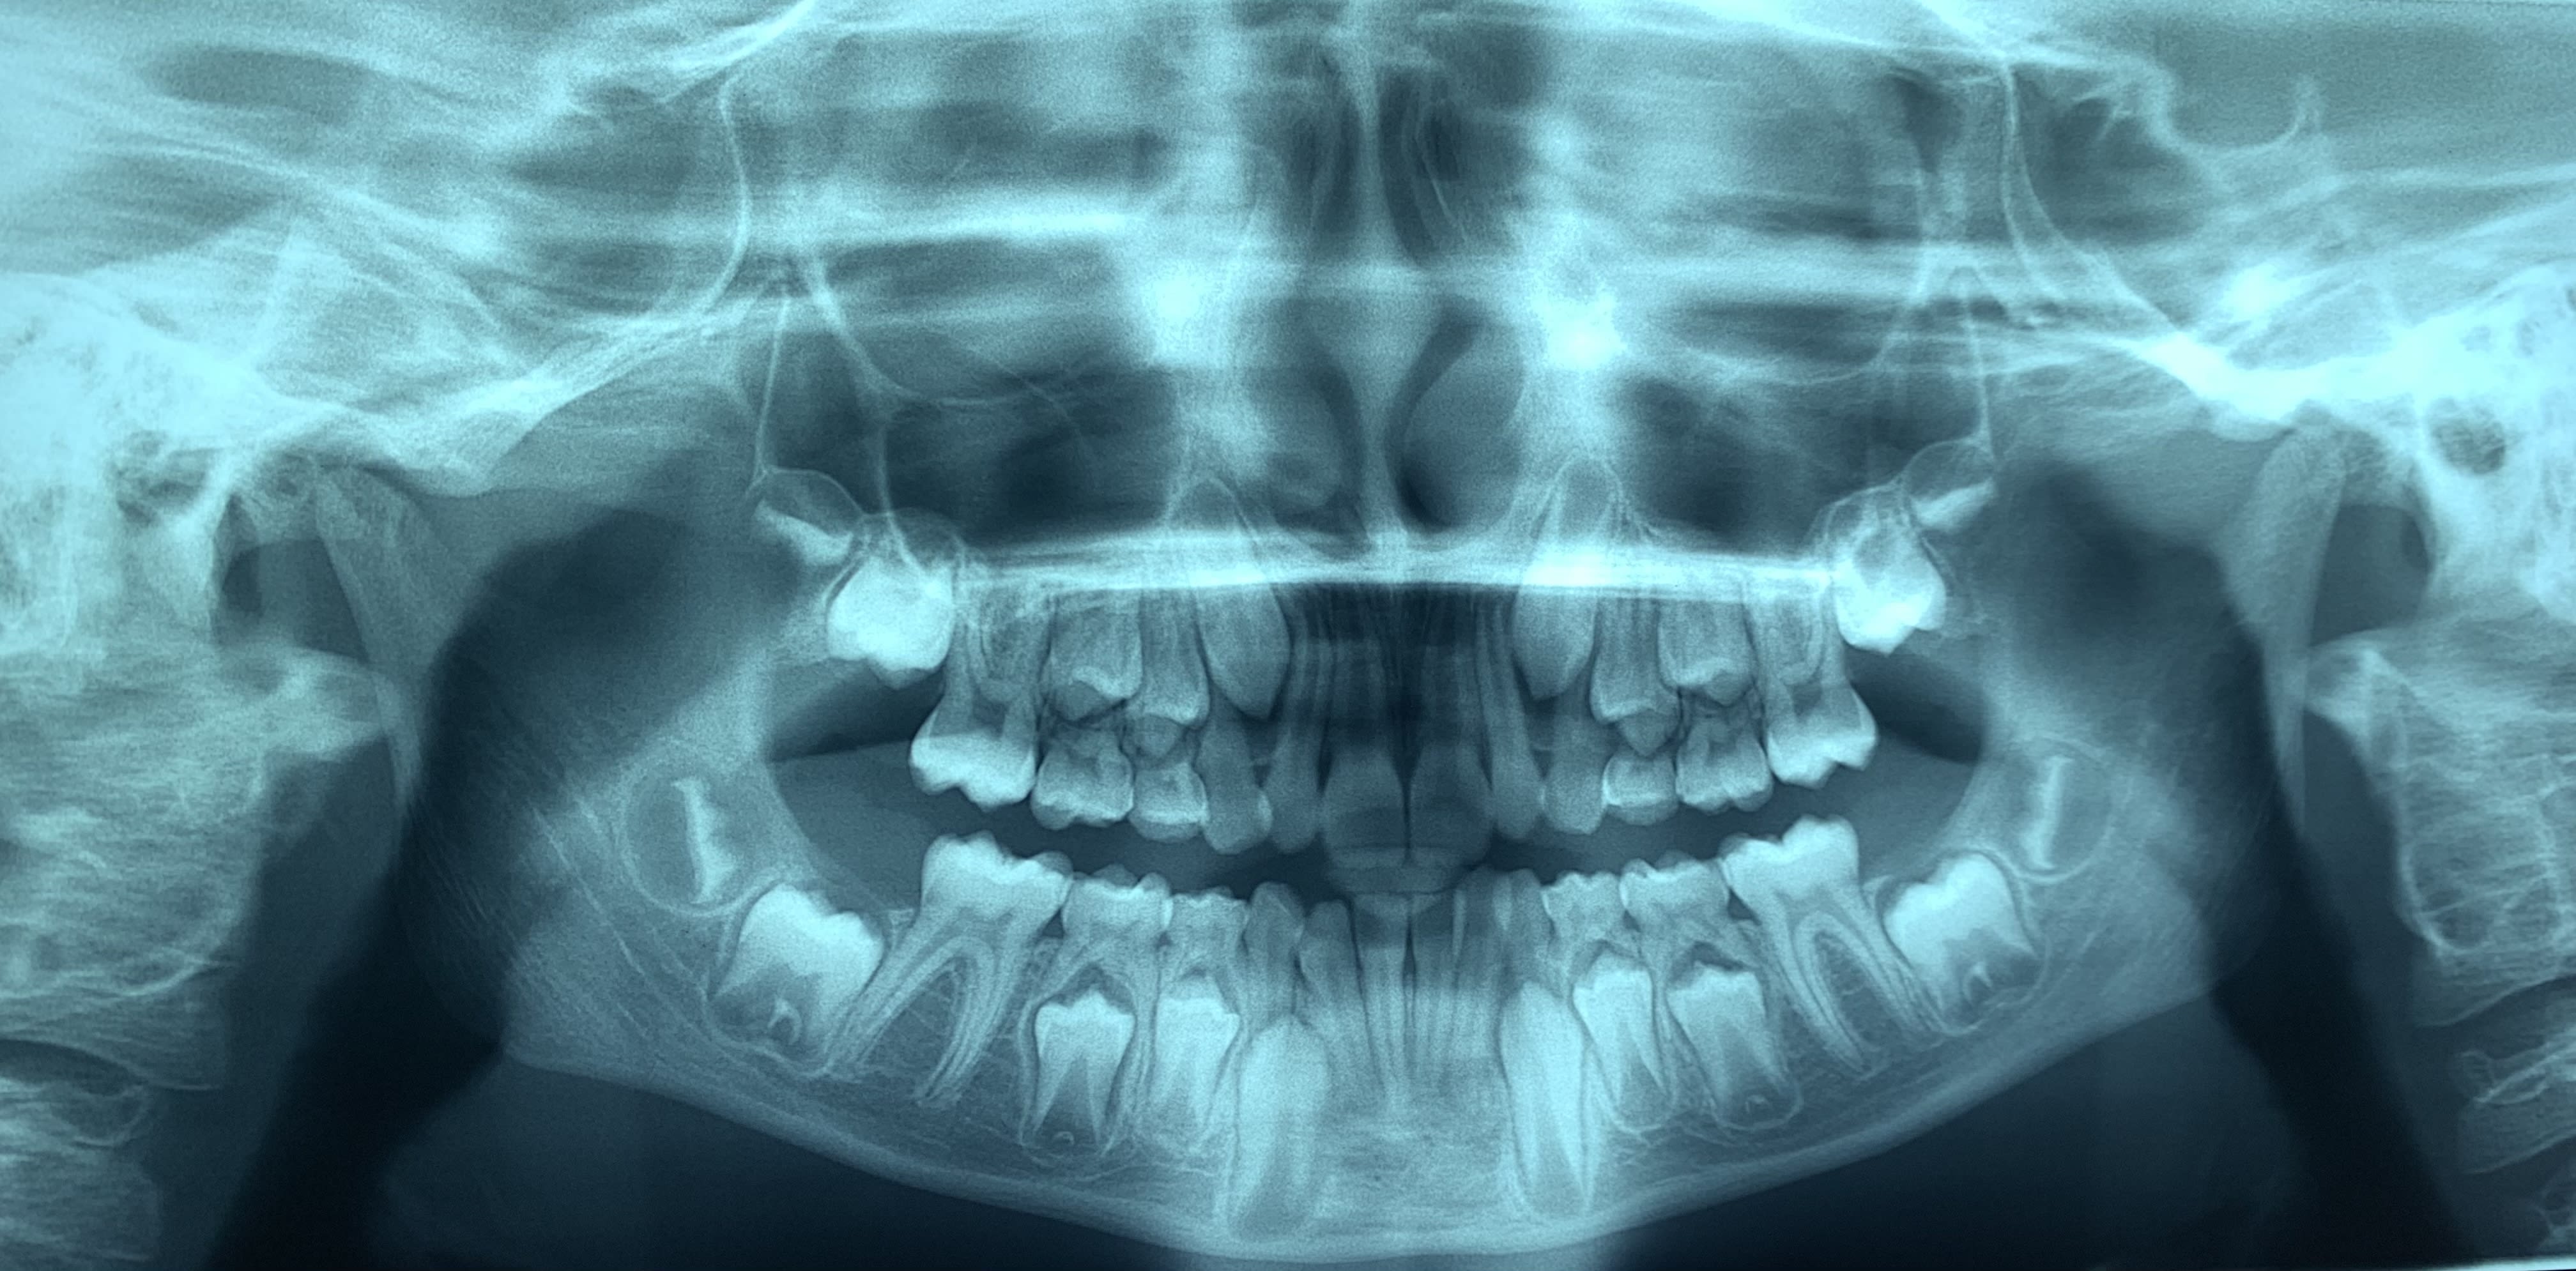

Normodivergent, classe I squelettique

Retroalveolie incisives centrales supérieures

DDM : signe de quintero maxillaire, 32 lingualee, manque d’espace

Classe 1 molaire, plan terminal de Chapman à marche mesiale

DDM antérieur (32 à 42) mesurée à 5mm, l’espace disponible du secteur moyen (III-IV-V) devrait, après calcul, être entièrement consommé par l’espace nécessaire à l’évolution des 3-4-5 définitives.

Pas d’inverse d’occlusion, distance 6-6 maxillaire = 35mm. Inclinaison coronolinguale des procès alvéolaires

Arcade maxillaire plutôt rectangulaire.

Je ne suis pas sûr qu'il soit obligatoire d'intervenir non plus. Ceci dit, pour faciliter les éruptions et préparer le terrain pour la suite, je ferais de l'expansion transversale (avec 2 plaques à vérin ou bien quadhelix et bihelix, selon les préférences du praticien).

C'est une Cl I DDM avec supraclusion inc.

Pour l'instant, Maintien du Lee Way: Nance max et AL mand. Il y a quelque chose à gagner.

Attente de définitives et suppression AL et Nance puis multi ht bas.